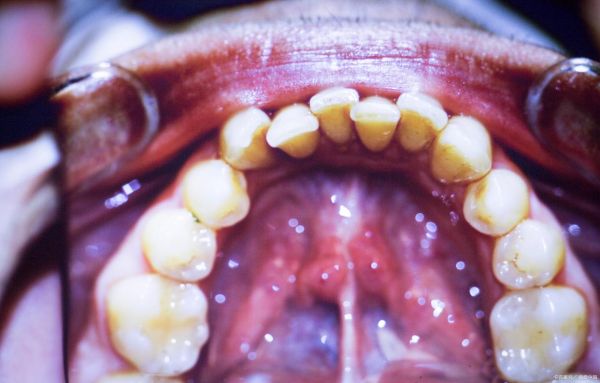

口腔中牙齒的狀況,猶如反映口腔健康的風(fēng)向標(biāo),同時也是衡量全身健康狀況的一個關(guān)鍵信號。你可能還沒察覺到,牙齒的完好程度與我們的壽命長短有著不可分割的聯(lián)系。長期以來,牙齒僅僅被視為用來咀嚼和說話的工具,而忽略了它作為全身健康“鏡子”的作用。近年來的醫(yī)學(xué)研究表明,牙齒的健康狀況能夠反映出人體的許多潛在疾病,甚至預(yù)測一個人的預(yù)期壽命。

我們常說“病從口入”,事實上,許多慢性疾病的癥狀最早可以從口腔表現(xiàn)出來,尤其是牙齒的變化??谇粌?nèi)的齒牙不僅是進(jìn)食時的研磨器,更是反映整體健康水平的晴雨表。通過觀察牙周健康、牙齒的脫落情況和磨損程度,可以從側(cè)面反映出一個人的生活方式、飲食習(xí)慣、精神狀態(tài)等多方面的健康信息。

口腔健康,不僅是衡量我們生活品質(zhì)的重要指標(biāo),更是反映全身健康狀況的一面“鏡子”,緊密相連,不容忽視。它悄悄記錄著我們的健康歷程,也無聲地提示著我們該如何為自己的長壽護(hù)航。